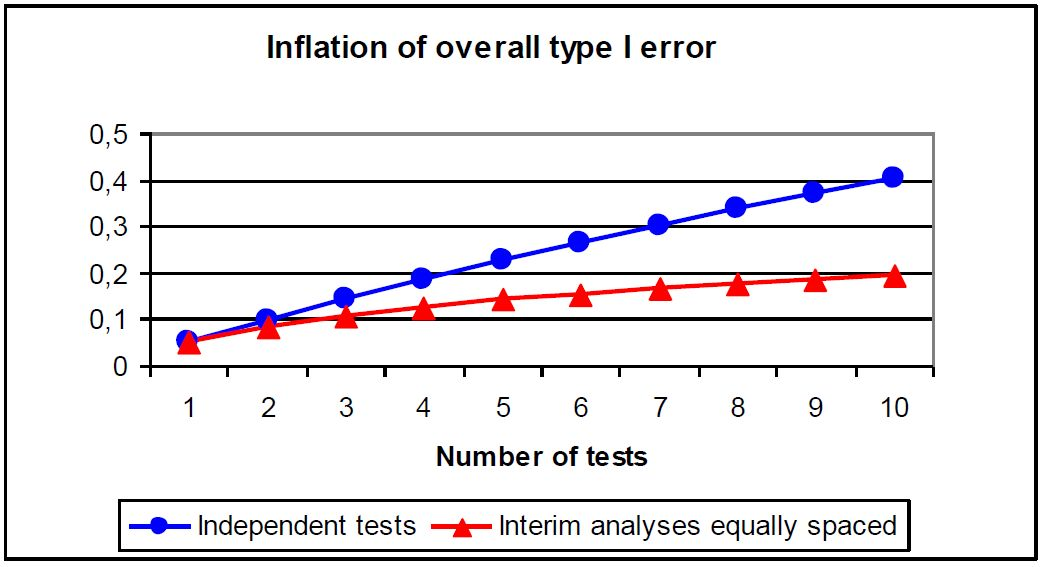

иҷҪ然дјҳејӮзҡ„жңҹдёӯеү–жһҗеҸҜд»ҘдёәдёҙеәҠиҜ•йӘҢеёҰжқҘз§Қз§ҚеҲ©зӣҠ����пјҢдҪҶжңҹдёӯеү–жһҗ并дёҚжҳҜи¶ҠеӨҡи¶ҠеҘҪ����пјҢзҺ°е®һдёҠ����пјҢжҜҸдёҫиЎҢдёҖж¬Ўжңҹдёӯеү–жһҗ����пјҢеҚіжҜҸдёҫиЎҢдёҖж¬ЎеҒҮи®ҫзЈЁз»ғ����пјҢдјҡдҪҝеҒҮйҳіжҖ§пјҲfalse positiveпјүжҲ–Iзұ»иҝҮеӨұзҺҮеўһж·»����пјҢиӢҘжҳҜжҜҸдёҖж¬Ўжңҹдёӯеү–жһҗеқҮжҺҘзәіα=0.05зҡ„зЈЁз»ғж°ҙеҮҶ����пјҢйӮЈд№ҲжңҖеҗҺзҡ„жҖ»дҪ“αж°ҙе№ід№ҹе°ҶйҡҸзқҖзЈЁз»ғж¬Ўж•°иҖҢеҚҮй«ҳ����пјҢеҚіжҖ»Iзұ»иҝҮеӨұиҶЁиғҖ��гҖӮеҰӮеӣҫ6жүҖзӨә����пјҢеҒҮи®ҫжҜҸж¬ЎзЈЁз»ғжҳҜиҮӘеҠӣзҡ„����пјҢ5ж¬Ўеү–жһҗд№ӢеҗҺ����пјҢжҖ»Iзұ»иҝҮеӨұе°ұдјҡеҮҢй©ҫ20%����пјҢиҝҷжҳҜзҫҒзі»жңәжһ„ж— жі•жҺҘеҸ—зҡ„��гҖӮеӣ жӯӨдёәдәҶдҪҝжҖ»Iзұ»иҝҮеӨұжҺ§еҲ¶еңЁзЈЁз»ғж°ҙеҮҶαпјҲеҰӮ0.05пјү����пјҢеҲҷеҝ…йңҖж ЎжӯЈжҜҸдёҖж¬Ўжңҹдёӯеү–жһҗзҡ„зЈЁз»ғж°ҙеҮҶ����пјҢеёёз”Ёзҡ„зЈЁз»ғж°ҙеҮҶзЎ®е®ҡиҰҒйўҶжңүPocockжі•гҖҒO' Brien-Flemingжі•гҖҒPetoжі•еҸҠLan-Demetsж¶ҲиҖ—еҮҪж•°жі•зӯү��гҖӮдёүйЎ№з ”з©¶дёӯе”ҜдёҖеҜ№PFSдёҫиЎҢжңҹдёӯеү–жһҗзҡ„FURLONGйҖүжӢ©дәҶLan-Demetsжі•����пјҢеҖјеҫ—дёҖжҸҗзҡ„жҳҜ����пјҢиҷҪ然FURLONGиҫғFLAURAе’ҢAENEASдёҫиЎҢдәҶжӣҙеӨҡж¬Ўзҡ„PFSеү–жһҗ����пјҢдҪҶе…¶з»ҹи®Ўж•ҲиғҪйҖүжӢ©дәҶ80%����пјҢдҪҺдәҺе…¶дҪҷдёӨдёӘз ”з©¶зҡ„90%����пјҢд№ҹеҜјиҮҙFURLONGзҡ„ж ·жң¬йҮҸзӣёеҜ№иҫғе°Ҹ��гҖӮ